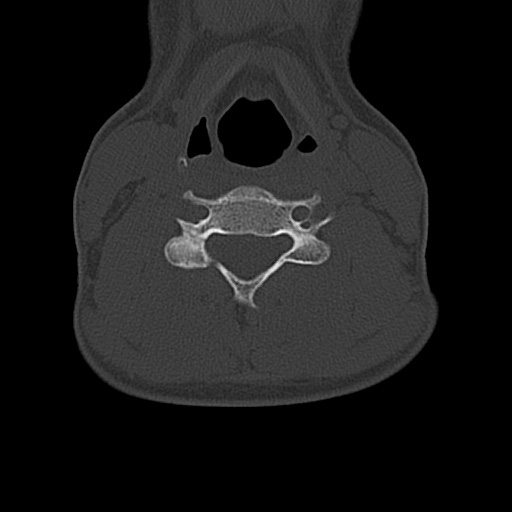

An x-ray of the right shoulder was negative and an MRI of the right shoulder showed no evidence of a rotator cuff tear. X-rays of the cervical spine showed straightening of the cervical lordosis and concern for a C5 lamina fracture. A CT of the cervical spine confirmed a fracture of the right C5 lamina extending into the right C5 facet Case Photo #1 . There was associated mild widening and mild unilateral subluxation of the right C4-C6 facet joints. An MRI of the cervical spine showed a small C5-C6 posterior disc osteophyte complex with moderate bilateral neuroforaminal narrowing. At C6-C7 there was a small central disc protrusion with no significant spinal canal narrowing. The nerve conduction studies revealed electrophysiologic evidence consistent with an active right C5 radiculopathy. There was no evidence of a focal entrapment neuropathy, right ulnar sensory response was normal and right median to radial sensory comparison study was normal.